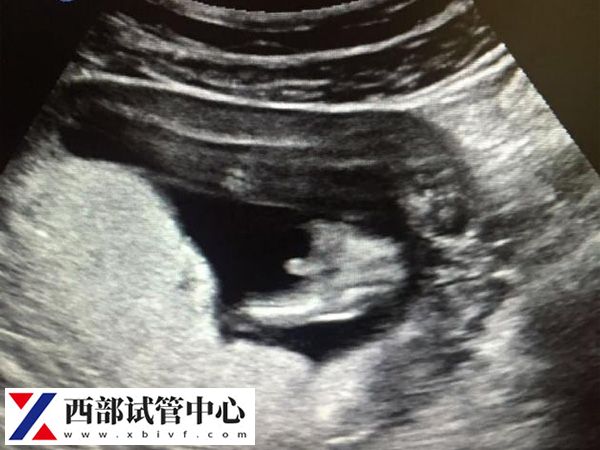

第二次超声检查

第二次B超是移植后的6-7周,检查是否有胎心的情况,再次确认单胎、双胎甚至三胎的情况,改成了解胎儿继续发育情况以调整黄体支持药物,少数情况下还有宫内宫外孕同时存在的情况。同时还要查看准妈妈宫腔内是否存在积液,如果积液较多,准妈妈就需要静养保胎,减少活动量,必要时准妈妈都有可能需要卧床保胎。